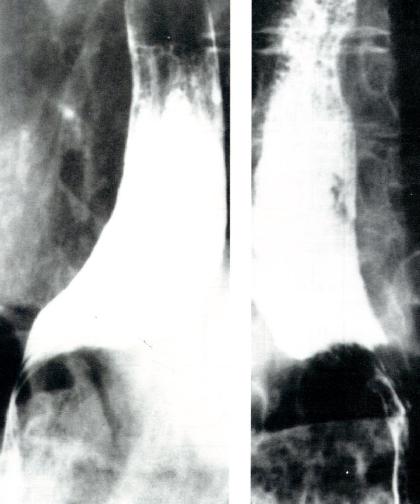

X线食管吞钡检查

食管体可呈扩张、张力低或直径正常但蠕动减少等不同的表现(图2.12)。

硬皮病患者的吞钡表现

图2.12硬皮病患者的吞钡表现。硬皮病X线所见可与贲

门失弛缓症相似,仅LES开口增大而不同。